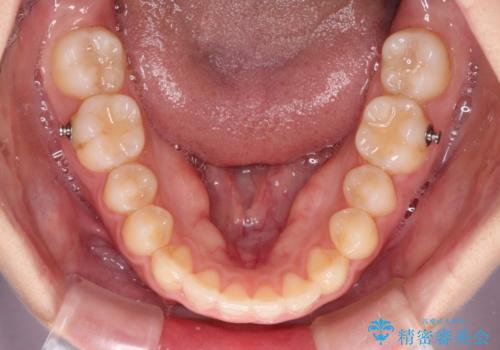

気になる残存乳歯と八重歯 ワイヤー矯正を併用したインビザライン治療

- 矯正装置

- インビザライン

- 八重歯を気にして来院された患者様です。

八重歯のために乳歯が残存していたため、乳歯を抜去して八重歯となっている犬歯を歯列に収めることとしました。

八重歯の移動量が多くなるため、インビザラインと併用してワイヤー矯正を行い、八重歯を改善した後に、上下歯列をインビザラインで整えることとしました。

犬歯は歯根が長くて太いため移動に時間がかかる上に、周囲の歯が八重歯に寄ってきてしまうため、仕上がるまでに期間がかかりました。